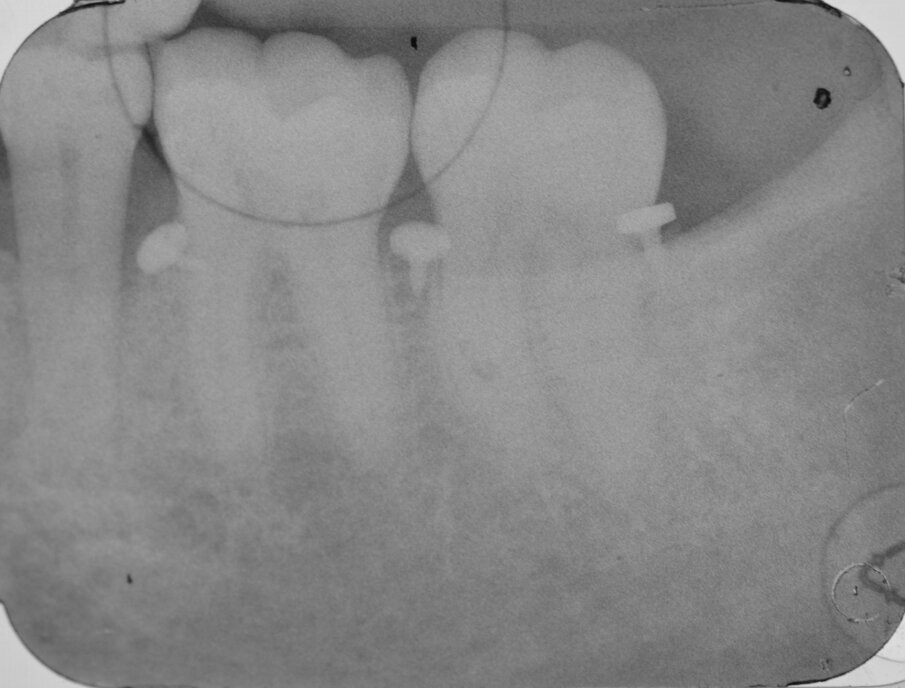

Dai sondaggi parodontali e dalle indagini radiografiche di 1° e 2° livello si evidenzia la presenza di un difetto intraosseo ampio e profondo che interessa la radice distale dell’elemento 3.7 nel suo aspetto disto-buccale; è assente il coinvolgimento della forcazione radicolare (Figg. 1-4).

Fig. 4 - RX preoperatoria che evidenzia il difetto osseo sull’elemento 3.7.